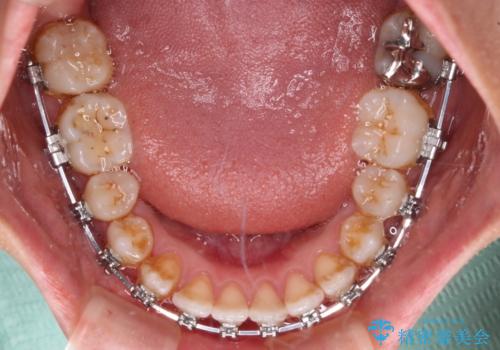

- 矯正装置

- メタルブラケット

上顎歯列および上顎骨が下顎に対して狭小であることが原因であるため、上顎の急速拡大装置を使用して上顎骨を側方に拡大することで反対咬合を改善し、ワイヤー装置で歯列を整えることとしました。